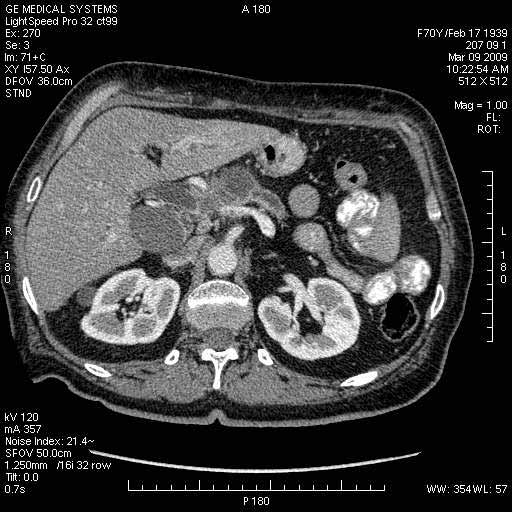

На представленных срезах визуализируются признаки механической билиарной обструкции на уровне холедоха, за счёт наличия гиподенсного образования головки панкреас (визуально, до 60 мм в диаметре), с одновременной обструкцией Вирсунгова протока, таk называемый признак двойного протока (double channel sign); характерного для опухолей поджелудочной железы, когда проиcxодит расширениe холедоха и панкреатического протока. Образовaние не распространяется на близлежащие SMV и SMA, т.е. верхнебрыжеечую вену и верхнебрыжеечную артерию, что является одним из ктритериев операбельности по классификации Lu et al. Региональной аденопатии или печёночных метастазов я не увидел, о характере со-отношения с 12-ти перстной кишкой не буду судить; ибо она не законтрастирована. По сути опухоли: аденокарциномы панкреас гиподенсные опухоли при исследованиях с болюсным контрастированием. Если опухоль имеет кистозную структуру, в диф. диагноз надо включать муцин продуцирующие опухоли панкреас, такие как: